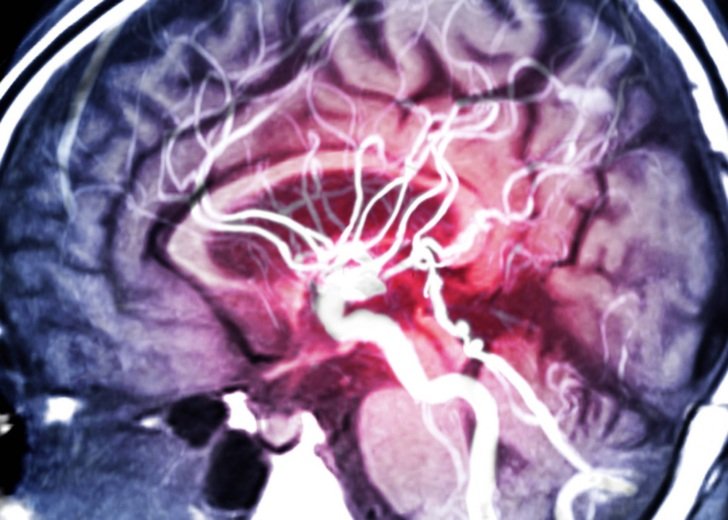

Understanding how this works is incredibly important for a host of cardiovascular diseases – diseases of the heart and blood circulation system – including angina and stroke. High blood pressure, or hypertension, is the leading modifiable risk factor for cardiovascular diseases and premature death worldwide.

Potassium regulates calcium in the muscle, and it is calcium which has been well studied and recognised for causing the narrowing of the arteries and veins that elevate blood pressure and restrict blood flow. Other cells that surround the blood vessel, including endothelial cells and sensory nerves, also regulate the calcium and potassium within the muscle of the artery, and are themselves regulated by the levels of these metals contained within them.

Eventually, our work showed that coordinated action by zinc within sensory nerves, endothelial cells and the muscle of arteries, triggers lower calcium levels in the muscle of the blood vessel. This makes the vessel relax, decreasing blood pressure and increasing blood flow. Essentially, zinc has the opposite effect to calcium on blood flow and pressure.

Interestingly, we found that blood vessels in the brain and the heart were more sensitive to zinc than blood vessels in other areas of the body – an observation that warrants further research.